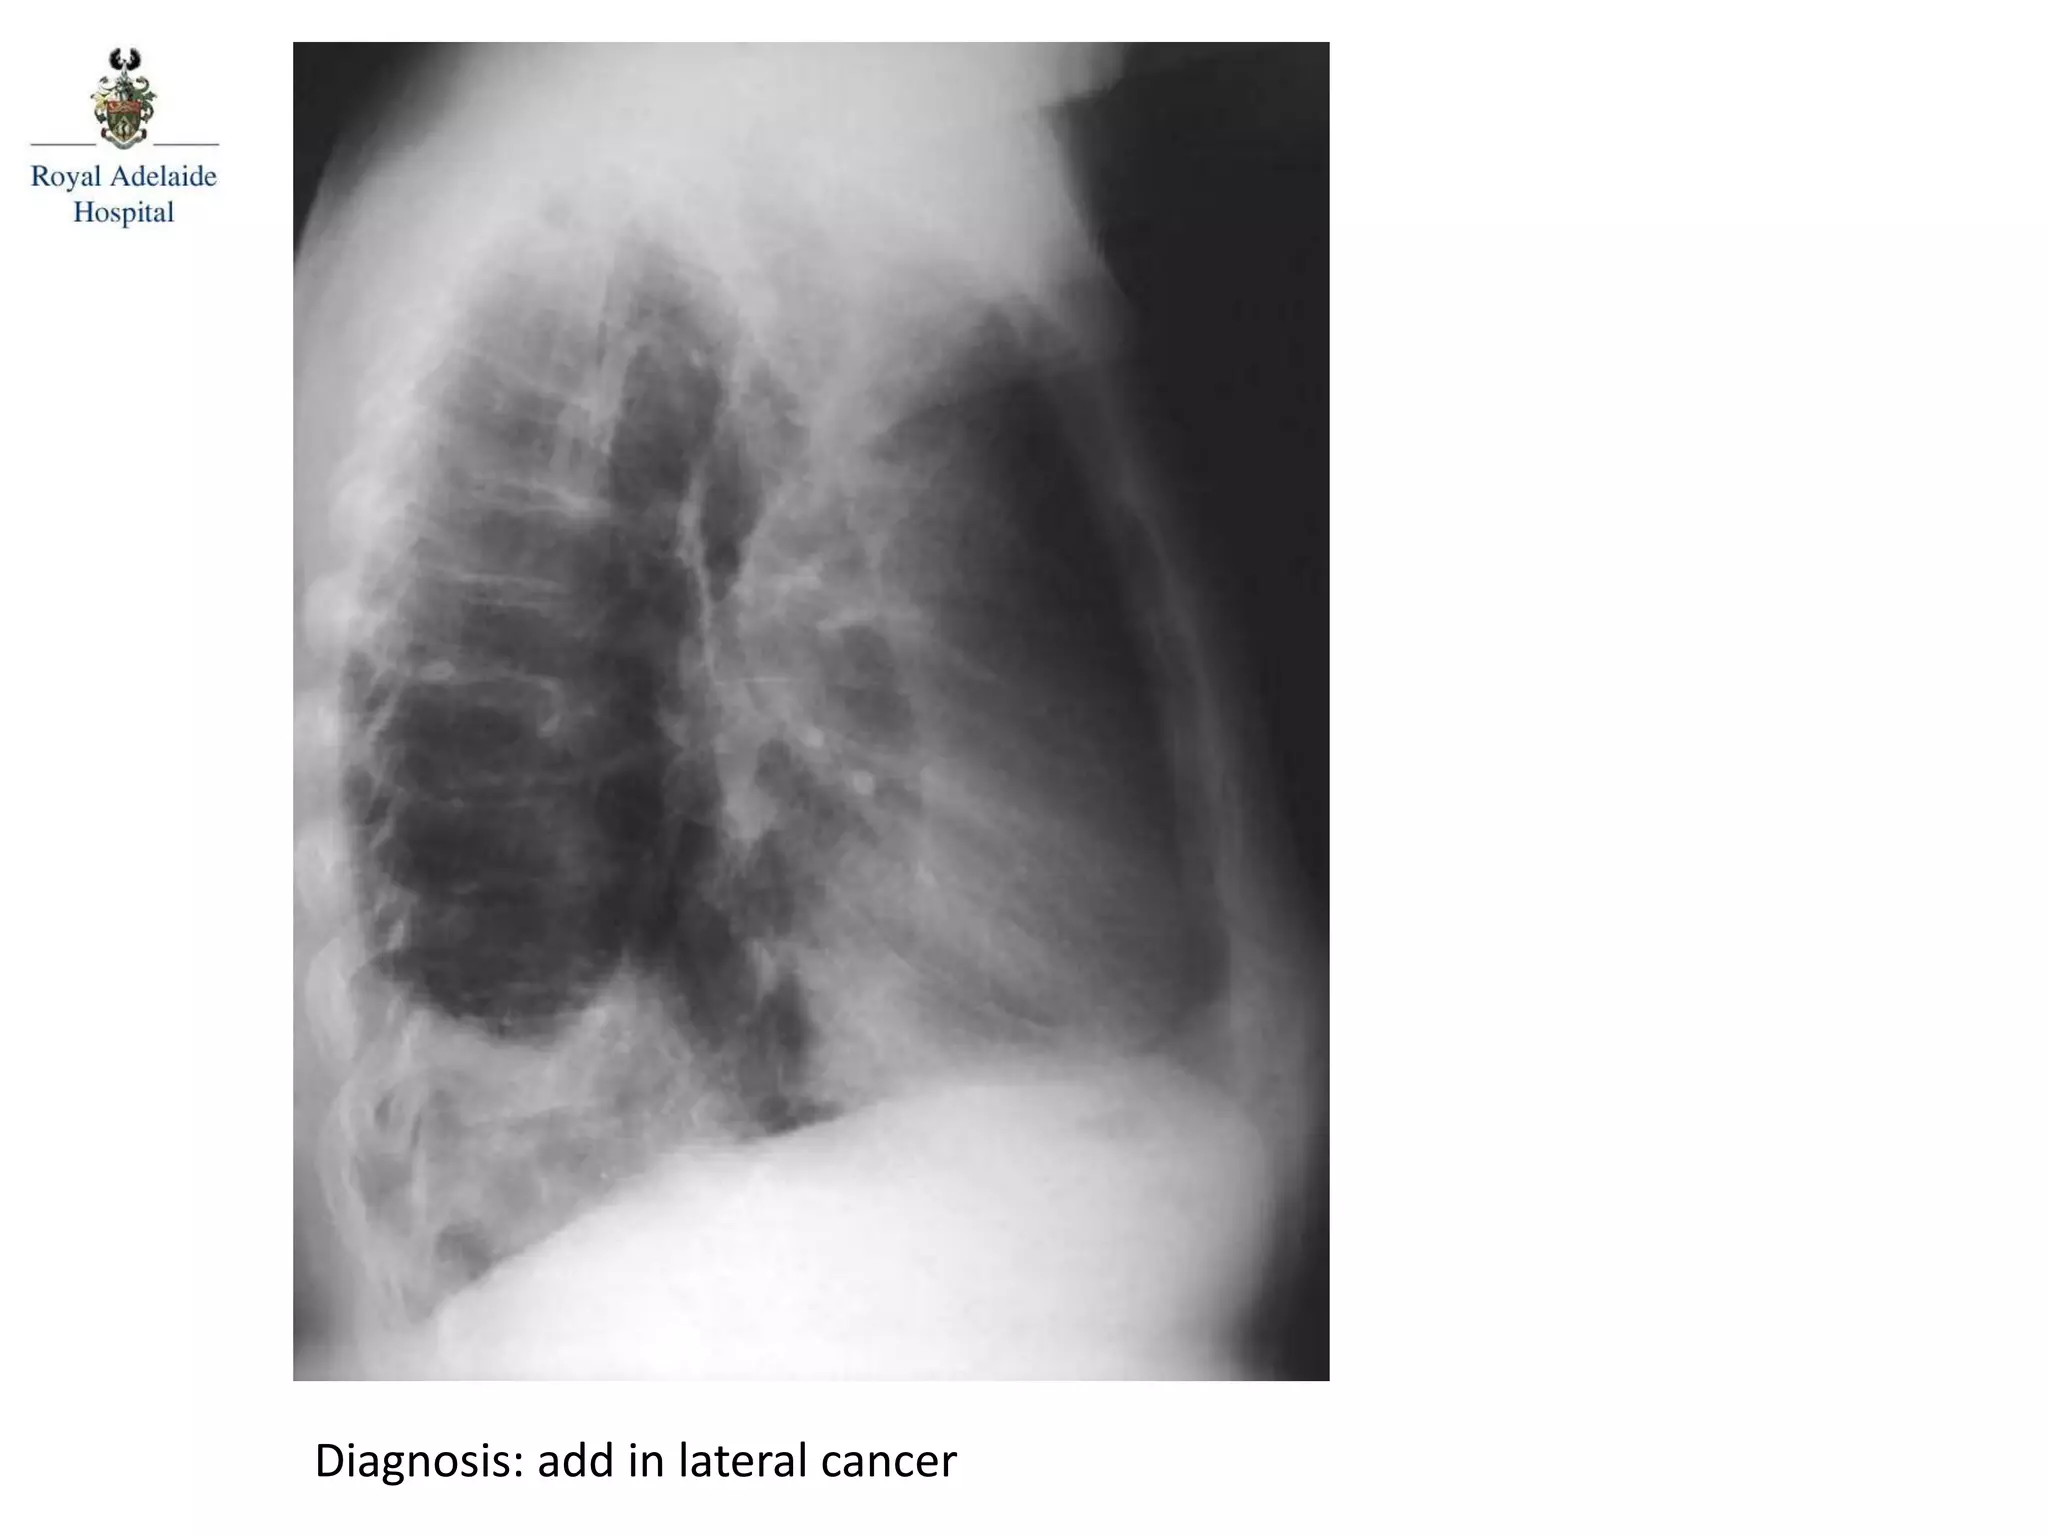

Diagnosis: add in lateral cancer